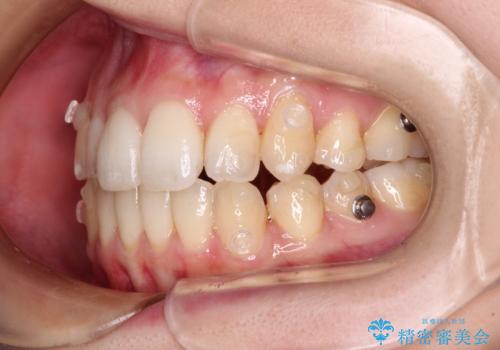

補助装置を併用したインビザラインでの八重歯の抜歯矯正

インビザラインによる矯正治療を希望されたため、八重歯改善のための抜歯矯正部分は補助装置を併用し、その後はインビザラインにて行うこととしました。

下顎の右側変位が顕著であったため、ワイヤー矯正の方が咬み合わせは改善しやすいのですが、ある程度は時間がかかっても良いとのことであったので、インビザラインにて矯正治療を行うこととしました。

骨格的に下顎が右側に変位していたため、上下正中を合わせることは困難であることは分かっていました。それでも、なるべく合わせるようにとしたため、治療期間は長期間となりました。

長期間とはなりましたが、咬み合わせが改善され、患者様には大変満足していただきました。